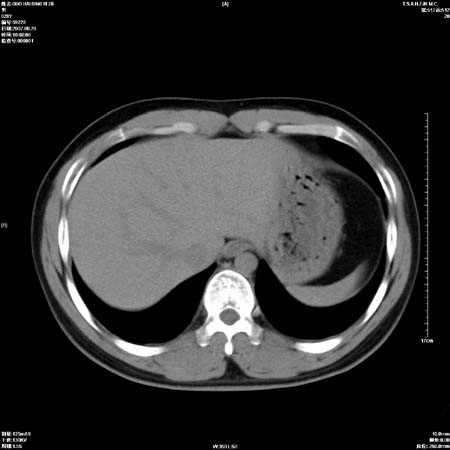

左肺中心型肺癌并纵隔淋巴结转移!考虑为小细胞肺癌,没有手术机会了,只能进行放化了,疗效不错,但极易复发。没办法,现在肿瘤年轻化越来越明显了。